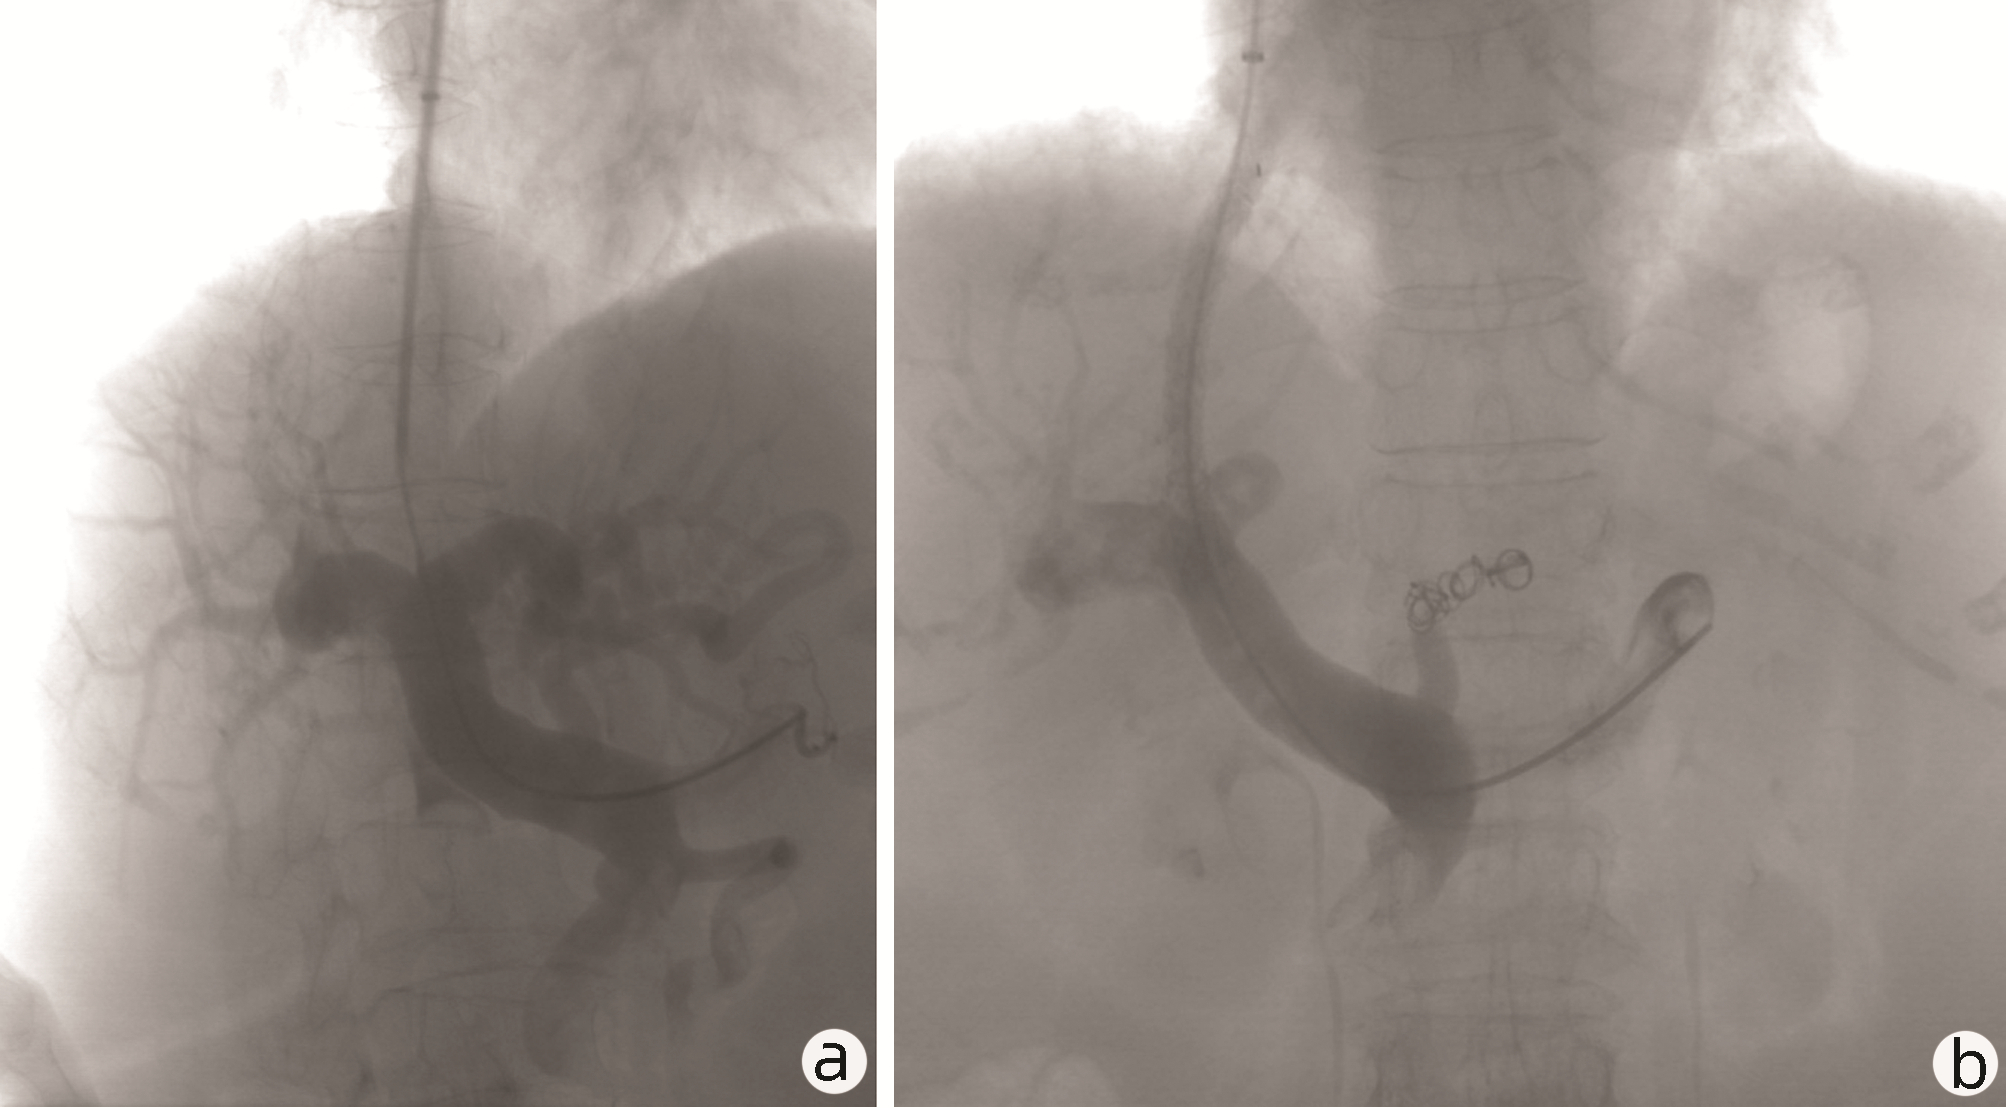

Bacteremia in an elderly patient with cirrhotic after transjugular intrahepatic portosystemic shunt: A case report

Qin LIU, Xin YAO, Ying LI, Sheng HE, Shanhong TANG, Jianping QIN

2022, 38(10): 2337-2340. DOI: 10.3969/j.issn.1001-5256.2022.10.025

Abstract(1041) HTML (240) PDF (2493KB)(62)

Abstract: